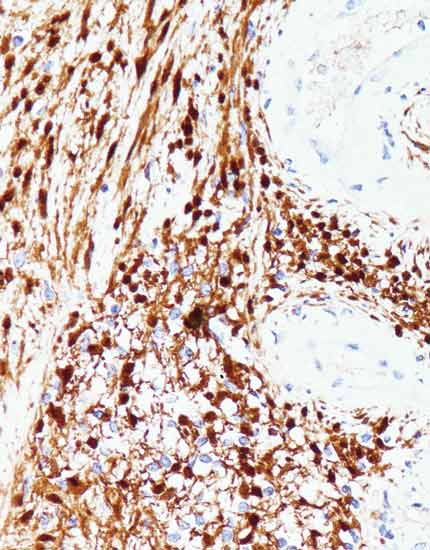

产品名称:S100

产品编号:Kit-0007

阳性部位:细胞质/细胞核

图片描述:

神经鞘瘤,S100染色,细胞质/细胞核阳性